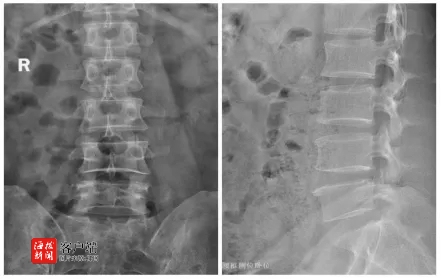

在仔细询问了李奶奶的病史后,孟教授又进行了一次全面而细致的体格检查,力求不错过任何可能导致疼痛的线索。经过深入的诊断,孟教授凭借他敏锐的医学洞察力,明确李奶奶患有腰椎椎管狭窄症,并用浅显易懂的语言,向李奶奶详细解释了她的病情,描述了腰椎椎管狭窄症的影响,以及它如何成为李奶奶长期疼痛的根源。

面对治疗方案的选择,孟教授提出了一项创新的微创手术——计算机导航下行斜外侧入路腰椎融合术。这种手术不仅能有效地缓解李奶奶的疼痛,还能恢复腰椎的稳定性。且手术创伤小,恢复期短。